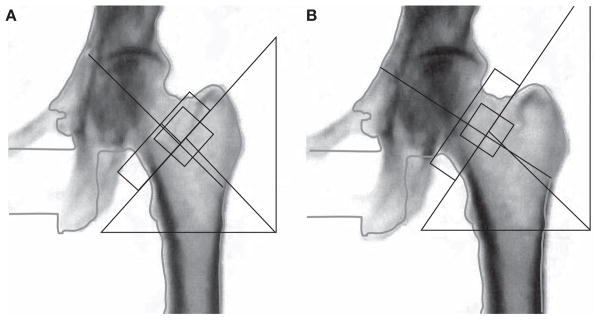

Scansione del femore prossimale

Per il femore, è essenziale indurre una rotazione interna dell’arto di circa 15-25 gradi utilizzando un apposito posizionatore per i piedi. Questa manovra serve a distendere il collo femorale, portandolo parallelo al piano di scansione e riducendo la sovrapposizione del grande trocantere.

Il piccolo trocantere deve essere minimamente visibile o assente in una scansione eseguita correttamente.

Le regioni di interesse (ROI) diagnostiche sono il “collo femorale” (Femoral Neck) e il “femore totale” (Total Hip). Il valore di BMD più basso tra i due deve essere utilizzato per la classificazione densitometrica.

L’area di Ward non deve essere usata per la diagnosi a causa della sua elevata variabilità e piccola dimensione.